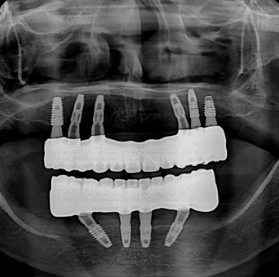

티타늄 바 케이스 (책에서 인용)

실제 환자분들의 깨끗한 통지르코니아 잇몸 반응

티타늄바는 꼭 필요한 경우에만 권해드립니다.환자분의 비용 부담을 줄이기 위해서입니다.

3년 내 보철이 깨지면 무상으로 다시 제작해드립니다. (필요시 티타늄바 넣어서)

원칙 지켜서 잘 만들면 지르코니아로 충분해요